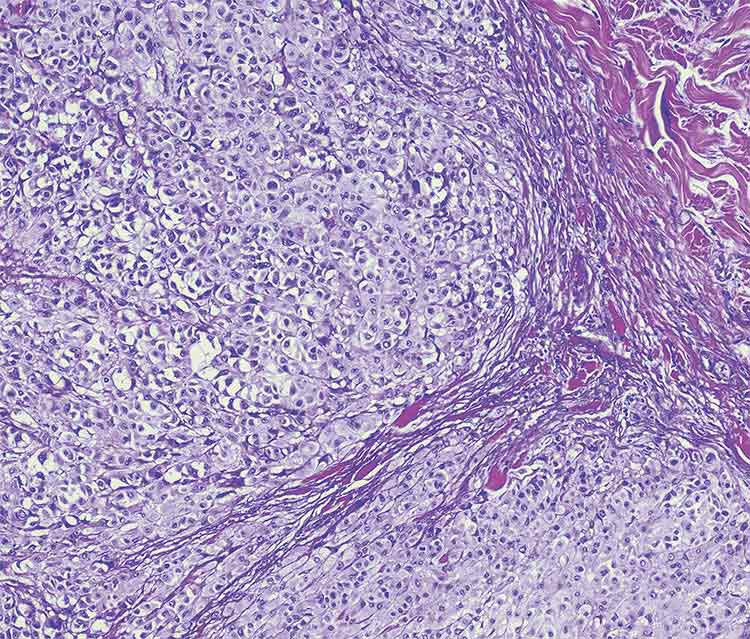

Metastatic melanoma. Courtesy of iStock.com/OGphoto

Metastatic melanoma. Courtesy of iStock.com/OGphoto.

In contrast to hardware integration, tandem Raman-LIBS can also be achieved by collecting data separately and merging it during analysis. Muhammad Nouman Khan’s group adopted this strategy in a biomedical context, studying formalin-fixed paraffin-embedded tissue samples to distinguish between melanoma and normal skin4. The goal of the research was to supplant traditional pathology techniques with instrumental methods requiring less sample preparation and operator training. They acquired Raman and LIBS spectra independently, then treated the combined data sets with machine learning techniques.

Normal skin and melanoma lesions differ in moisture and texture. Melanoma tissue is significantly drier and harder than normal tissue. Changes in water content and rigidity may be attributable to differences in the tissue’s main constituents. Additionally, surface hardening decreases the complexity of laser ablation on soft tissue by removing some of the impact of water quenching of plasmas, making successful LIBS signals easier to collect. The surface hardness may cause stronger spectral signals in the melanoma sample, as well as stronger calcium, magnesium, phosphorus, and potassium lines.

This approach highlights a different kind of complementarity. While Raman spectroscopy captures the biochemical characteristics of tissues — such as proteins, lipids, and nucleic acids — LIBS adds information about the presence of trace elements, influenced by tissue moisture. Together, the two methods offer a more comprehensive picture of the sample for diagnostics. Even though the measurements are taken on different instruments, data fusion enables accurate classification, demonstrating that spatial or temporal separation does not necessarily limit the value of combined analysis — provided the fusion strategy is robust.